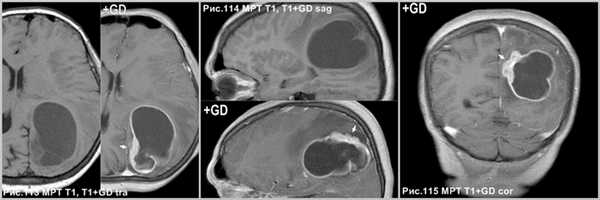

ПКА интенсивно накапливает контрастный препарат (стрелки на рис.110, 111 и 112). “Дуральный хвост” характерная особенность ПКА (головки стрелок рис.110, 112). Стенка кисты опухоли интенсивно накапливает контраст (стрелки на рис. 113-115).

Неравномерное и неоднородное накопление контрастного препарата. Может наблюдаться отсутствие контрастирования некоторых участков стромы опухоли. Патогномонично контрастирование прилежащей ТМО ("дуральный хвост") - как признак инфильтрации мозговых оболочек [2], Другое мнение, что это реактивные изменения, а не следствие прямого дурального вторжения, которое бывает редко [148]. Стенки кисты могут быть усилены или не накапливают контрастный препарат [48].